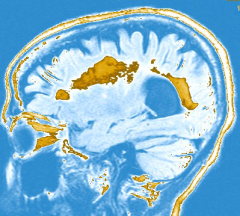

A Scenario: Meghan is a 22-year-old graduate student who is sent to the neurology office by the student health clinic with a chief complaint of pain and blurred vision in one eye. The neurological exam reveals decreased visual acuity in that eye and abnormal responses of the pupil to bright light. An MRI of the brain shows multiple lesions in the regions of the brain that carry connections, the cerebral “white matter.” In this MRI some of these lesions show enhancement with MRI contrast.